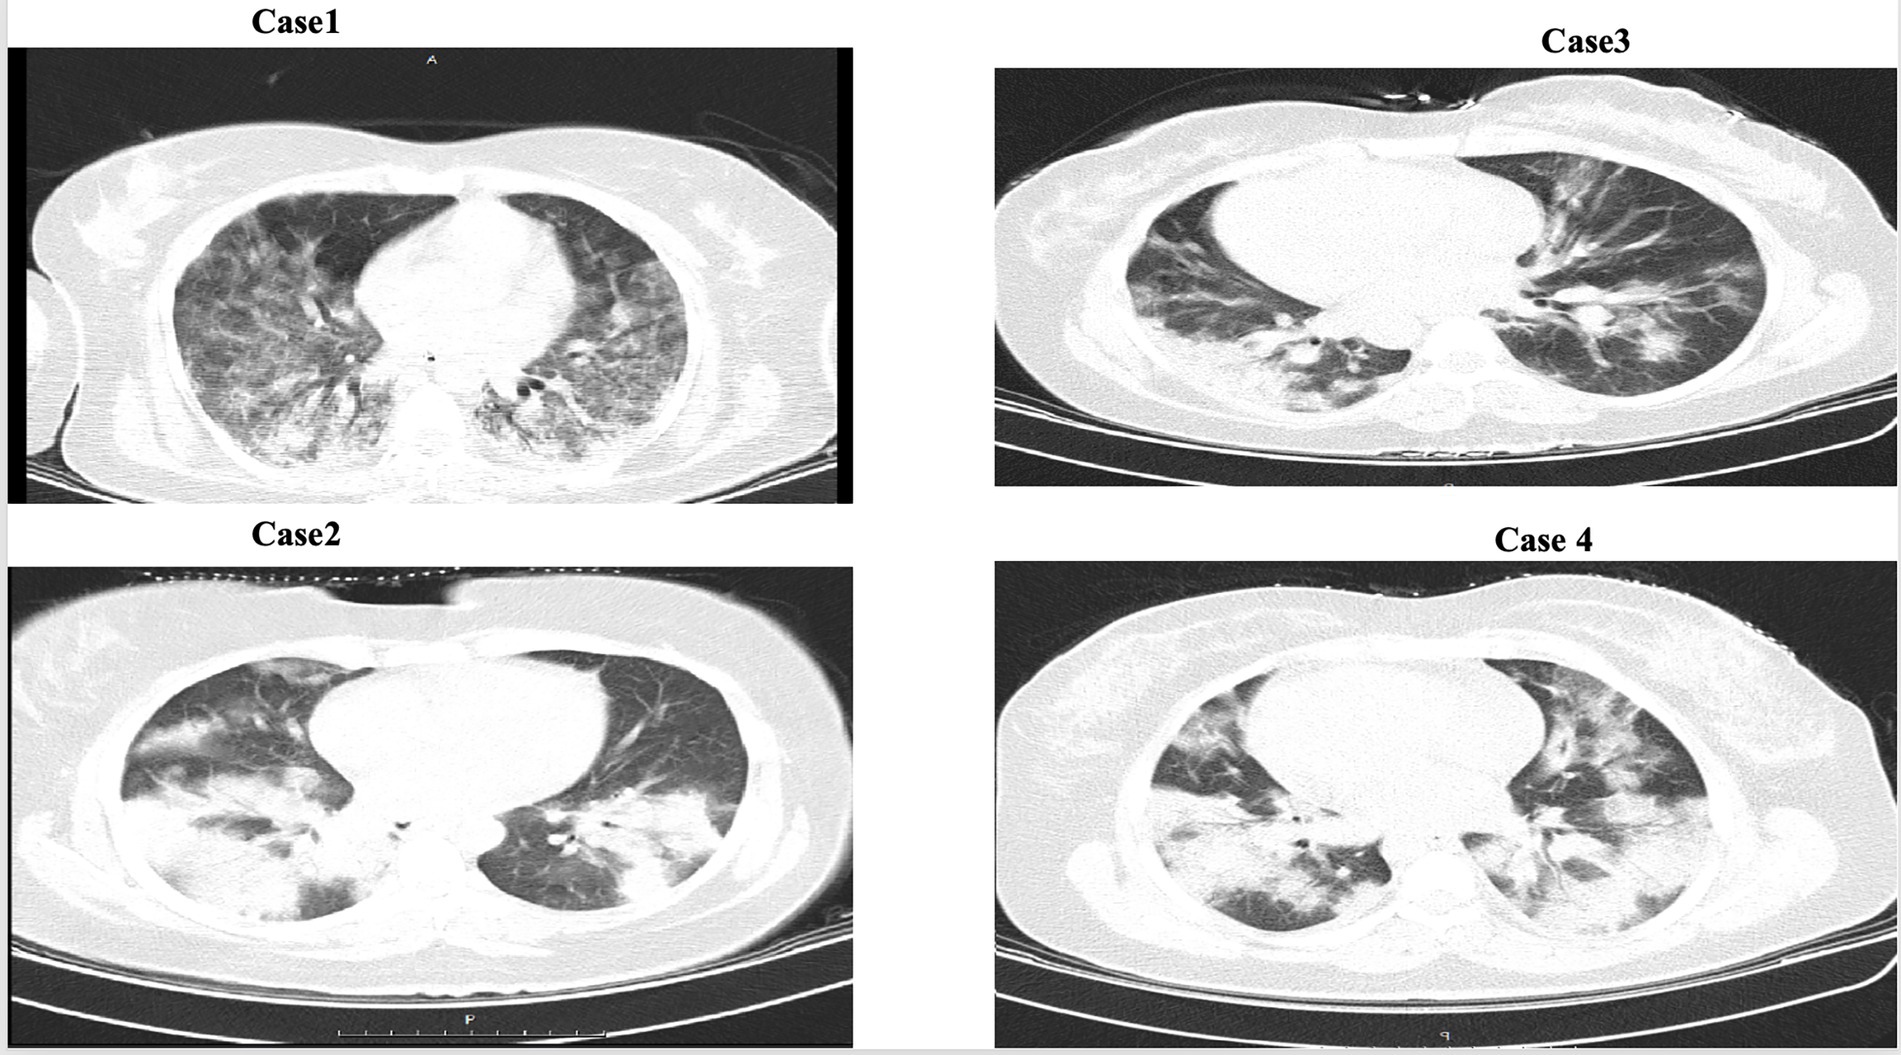

Figure 1

CT scan of the lung patients.

Our radiological findings, which showed patchy and ground-glass opacities on chest CT scans, are consistent with previous reports in pregnant patients with COVID-19 pneumonia (14). This underscores the importance of urgent supportive care and the crucial need to distinguish this condition from other pregnancy-related complications like preeclampsia.